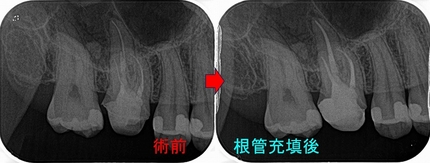

過去からのレントゲンを見ると

口蓋根の根尖に前は無かった根尖病変が現れています。

患者さんに、レントゲンを見せてクラウンだけ入れてもまたすぐに外す必要が出てきそうだから

この歯に関しては一度根管治療からやり直した方がいいと説明

2025 EEdental FRI (2).jpg

4根ガッタパーチャー使用 レジンコア+仮歯まで